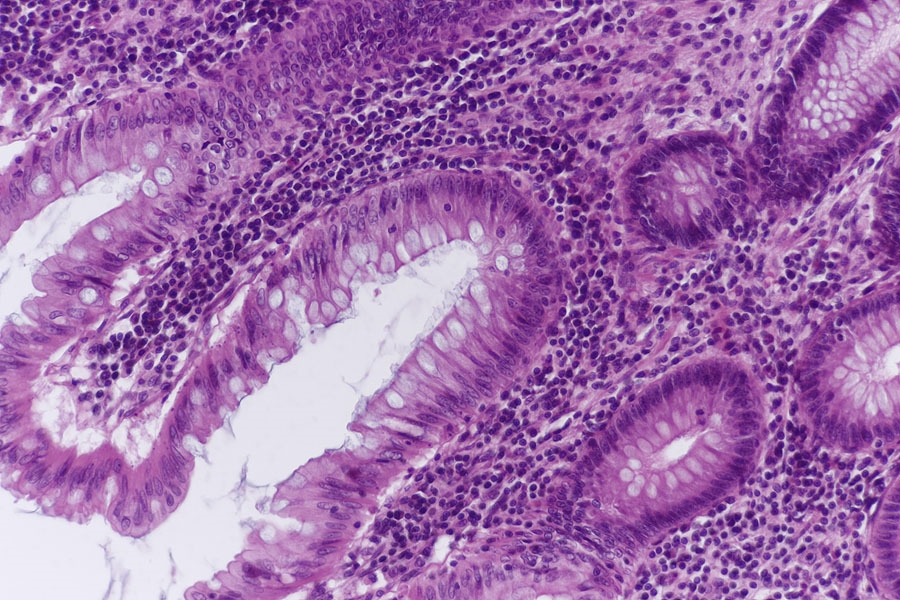

Es findet sich ein Darmabschnitt mit einer Mucosa die sehr viele Becherzellen enthält,

so wie einer breiten Submucosa. Auch hier sind die Sekundärfollikel nicht sehr ausgeprägt.

Epithel